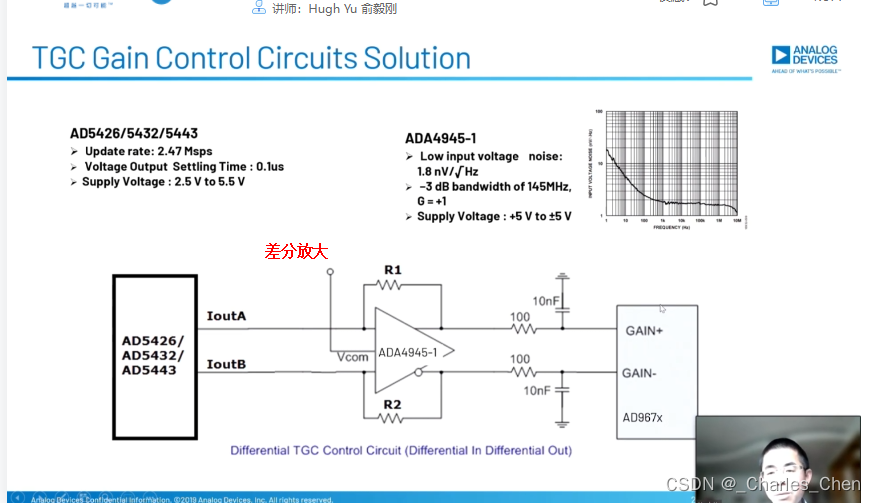

可变增益放大器(VGA)

VGA有时也称为时间增益控制(TGC)放大器,能够在整个接收周期内为接收机提供足够的动态范围。超声信号在体内大约每秒传输1540米,往返衰减率为1.4dB/cm-MHz。发射一个超声脉冲后,可立即在LNA输入接收到高达0.5VP-P的回波信号,该信号会快速跌落到传感器单元的热噪声基底。接收该信号所要求的动态范围约为100dB至110dB,超出了实际ADC的输入量程。因此,需要利用VGA 将信号转换成与ADC量程相当的信号幅度。典型应用中采用12位ADC,要求VGA能够提供30dB至40dB的增益。增益随时间调整(即“时间增益控制”),实现所要求的动态范围。

超声接收机的瞬态动态范围也很关键,它会影响2D图像的质量和系统检测多普勒偏移(血液或组织的运动)的能力,尤其是在二次谐波成像系统中,感兴趣的二次谐波信号明显低于发射信号的基波。对于小的多普勒信号同样如此,多普勒信号频率可能在1kHz以内,幅度远远低于组织或血管壁的反射信号。因此,需要特别关注可变增益放大器的带宽和近载波SNR,这些参数通常是制约接收机性能的关键。